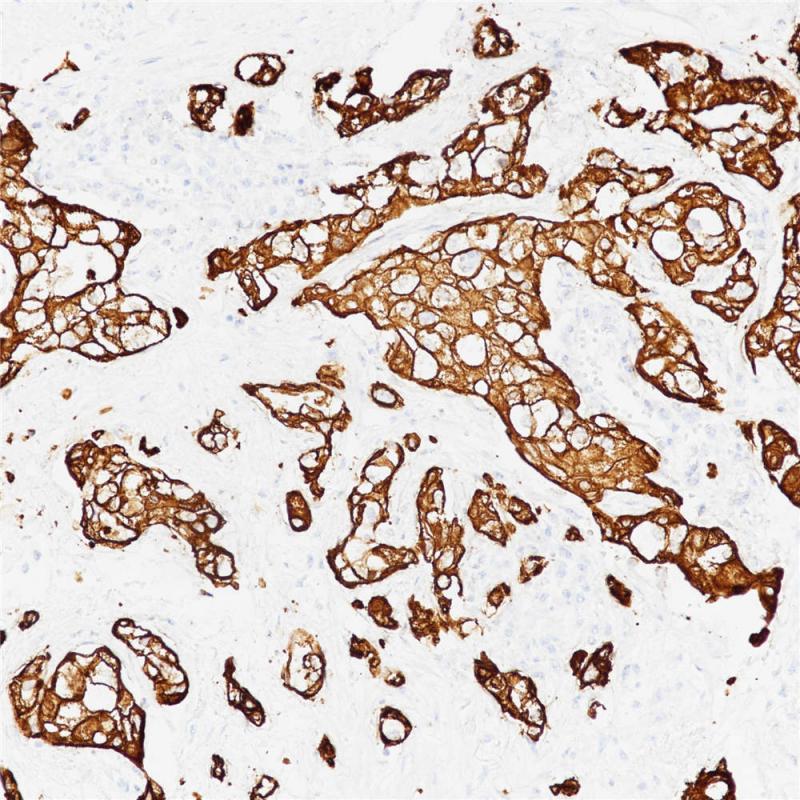

EGFR(L858R) 重组兔单克隆抗体

EFGR L858R为EGFR的其中一种基因突变类型,其突变主要发生在18/19/20/21外显子,21外显子编码的第858个氨基酸因为mRNA的第2553位密码子T置换为G使得编码氨基酸由亮氨酸(英文缩写为L)变成了精氨酸(英文缩写为R),上述突变引起EGFR下游通路的激活,导致肿瘤的发生。

阳性对照

肺癌

亚细胞定位

细胞膜/细胞质